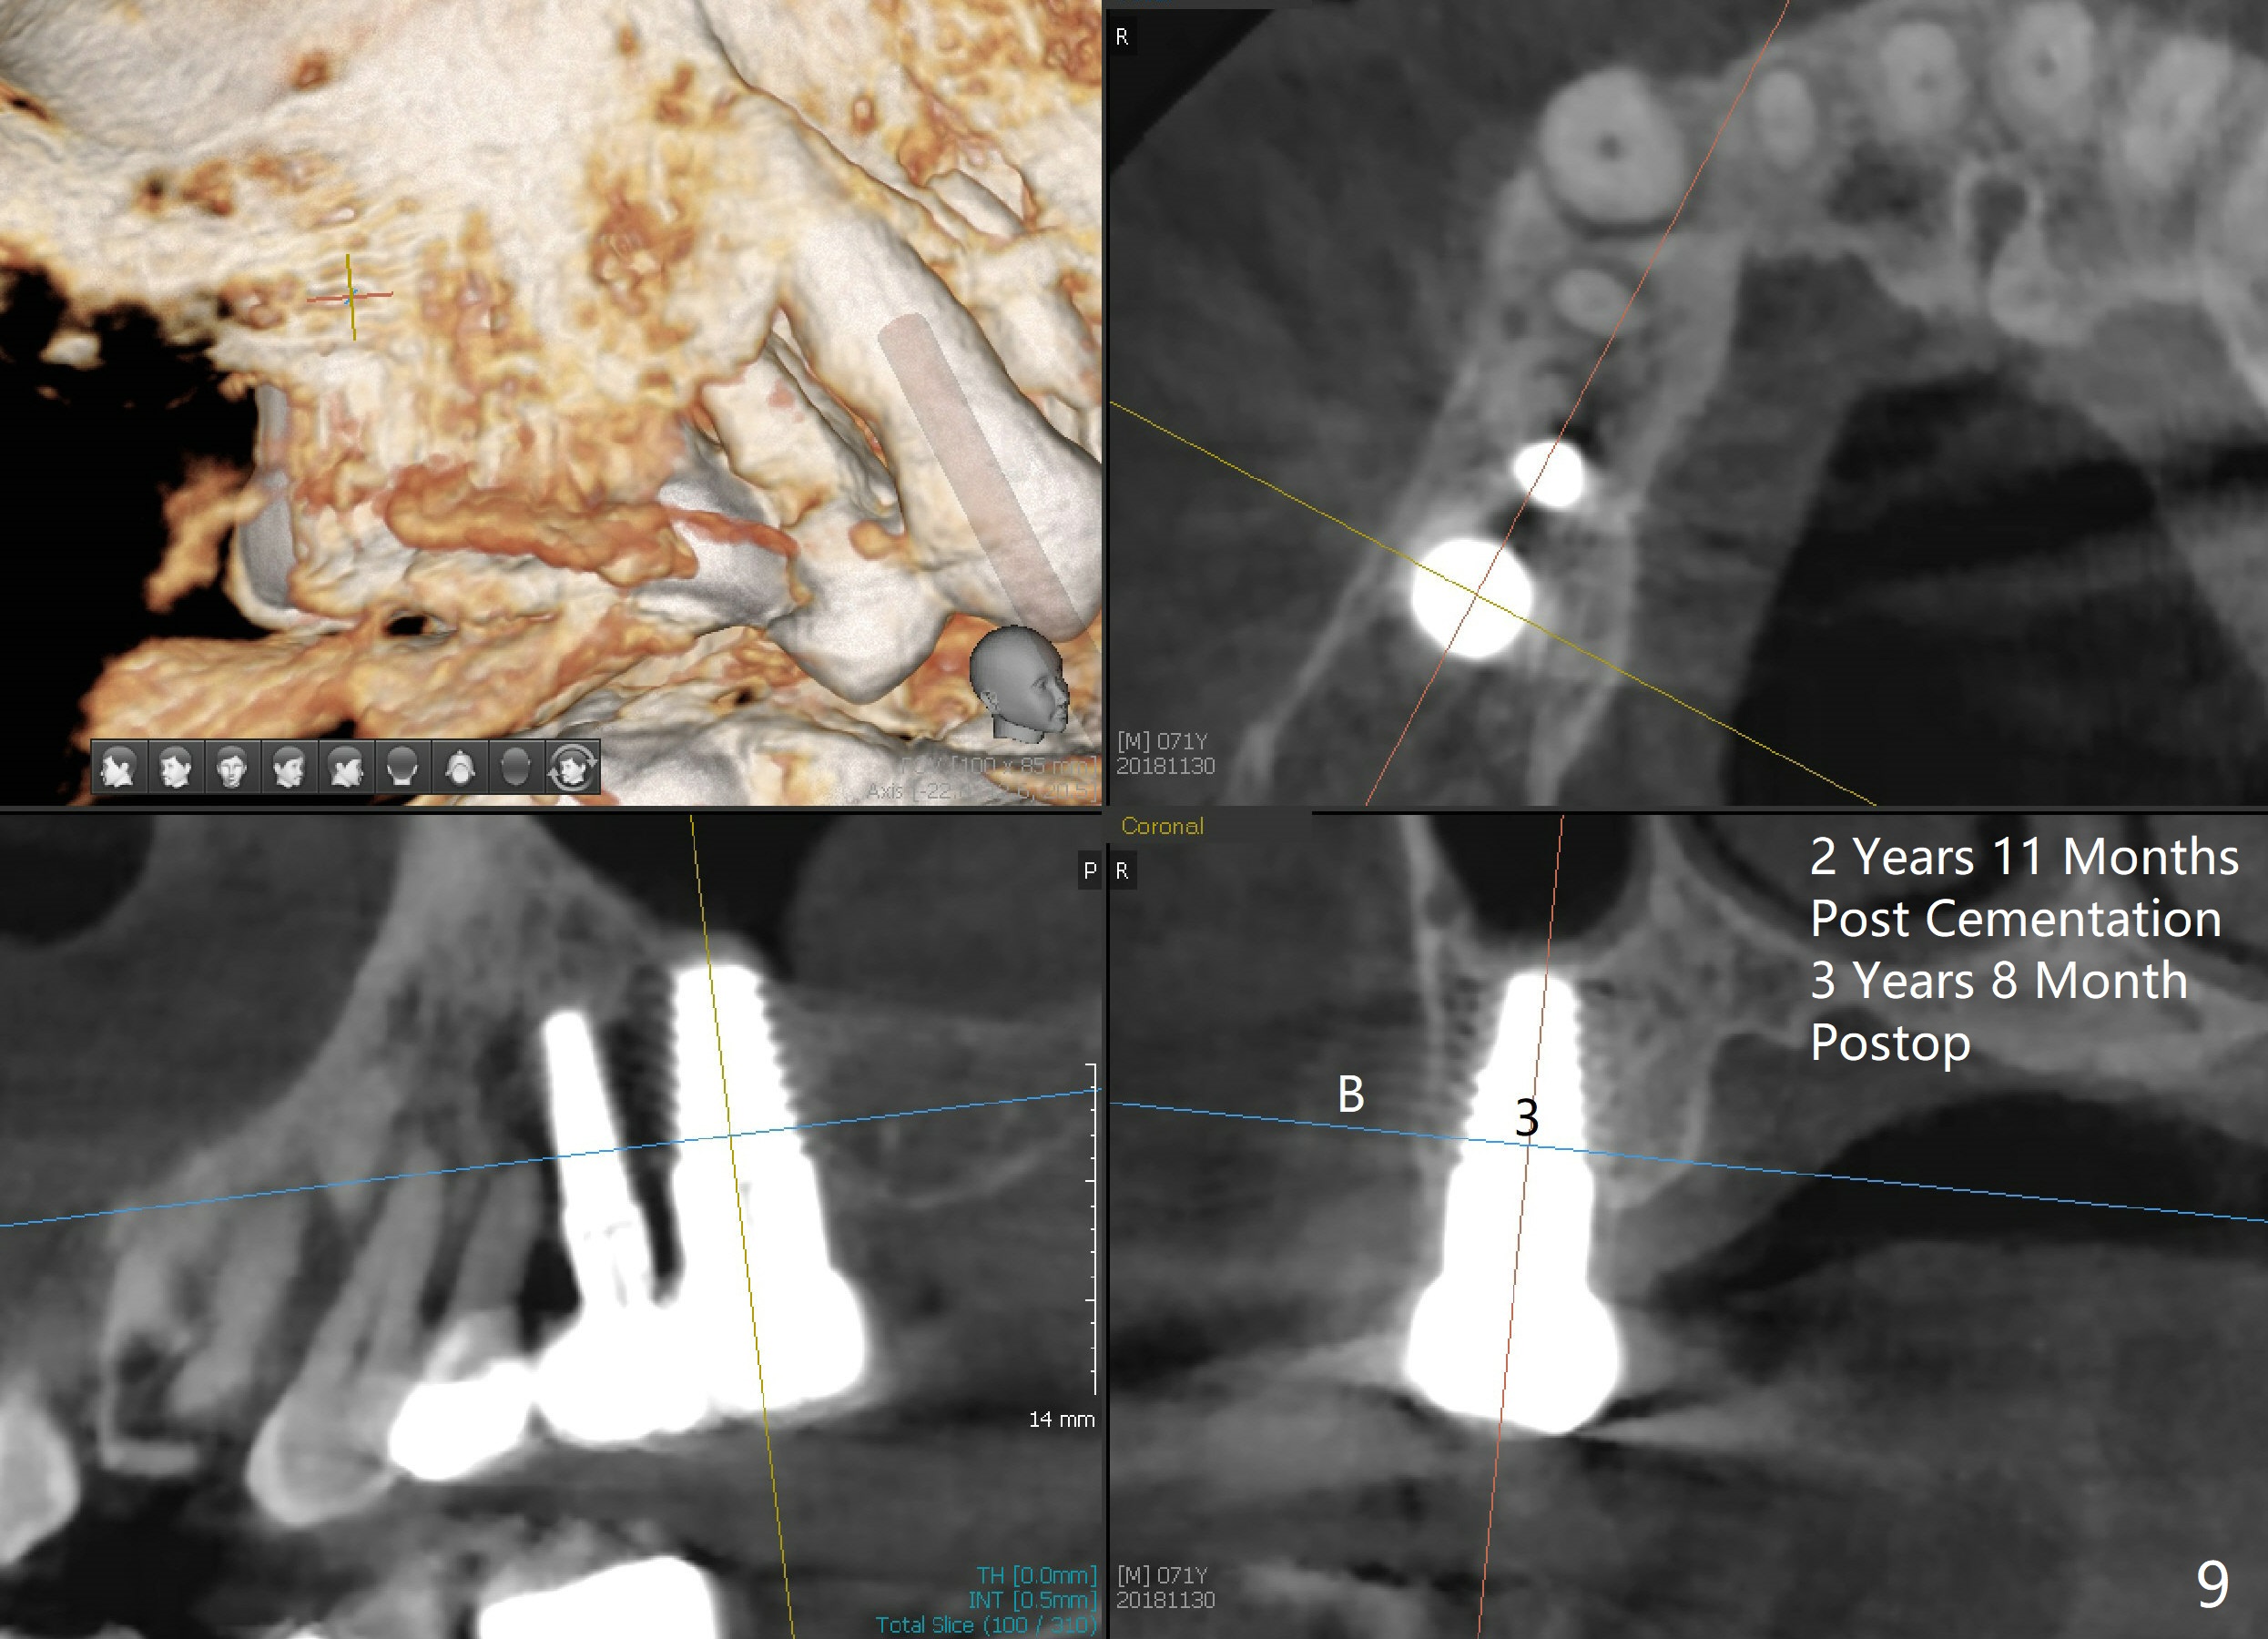

The flaps do not completely contact the implant when they are sutured. The wound needs protection during the initial postop stage. One of modes is to use perio dressing. The latter is not retentive in the distal edentulous area. Addition of a short abutment (Fig.7 A) over the implant should increase the retention of perio dressing (Fig.8) while micromovement of the implant is minimal. The tooth #30 is missing. There is no bone resorption 2 years 11 months post cementation (Fig.9).